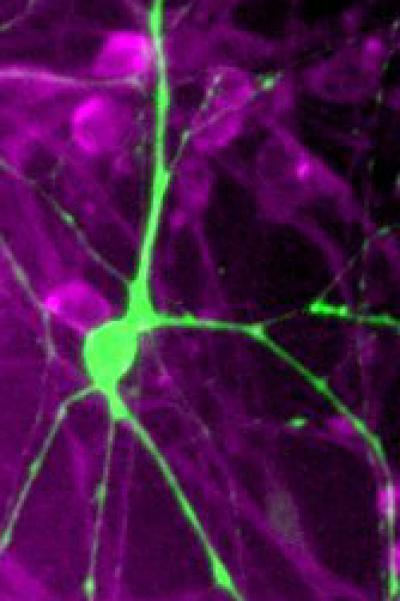

NIH-funded scientists show that the deadly Parkinson's gene LRRK2 can kill nerve cells (green) by tagging the s15 ribosomal protein (purple), a cog in a cell's protein-making machinery.

(Photo Credit: Courtesy of Dawson lab, JHU Morris K. Udall Center of Excellence for Parkinson's Disease.)